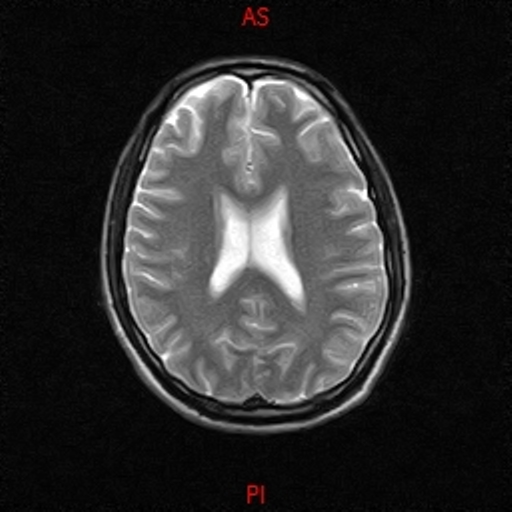

• Resonancia NORMAL CRANEAL T2 AXIAL

• Resonancia NORMAL CRANEAL T1 SAGITAL

• Resonancia NORMAL CRANEAL T1 AXIAL